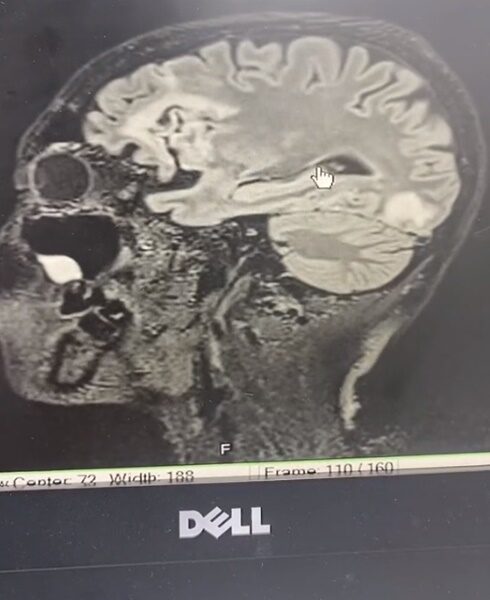

โดยยกเคสผู้ป่วยหญิง สาวโสด วัย 57 ปี มีอาการพูดจาสับสน ญาติรีบพามาปรึกษาแพทย์ ตรวจ MRI พบเนื้อสมองตายหลายจุด

ในบางตำแหน่งทำให้ตามัว และตำแหน่งสมองซีกซ้ายที่ควบคุมภาษา ส่งผลให้การพูดต่างไปจากเดิม นอกจากนี้ ยังพบจุดเลือดออกในหย่อมที่พบสมองตายด้วย